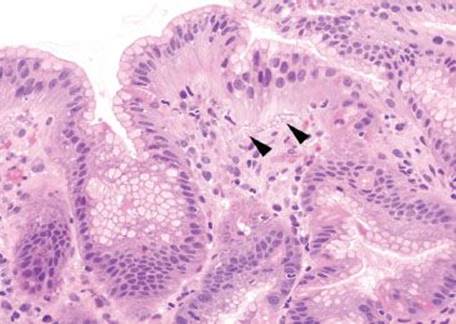

Gastric iron deposition is seen in up to 3.8% of upper tract biopsies (Fig. 2.228).23,24,183–185 In a study of 500 gastric biopsies, the deposition was demonstrated in three generalized patterns. Pattern A (also referred to as “nonspecific gastric siderosis”) was the most common subpattern and involved 2.2% of specimens (Figs. 2.229 and 2.230). This subpattern was associated with prior mucosal microhemorrhages, and the subtle depositions were predominantly identified within macrophages and stromal cells of the lamina propria. Pattern B (also referred to as “iron pill gastritis”) was seen in 0.8% of the biopsies and was consistently associated with ferrous sulfate therapy. This deposition was coarse and crystalline and predominantly identified in the extracellular and most superficial aspect of the biopsy (Figs. 2.231–2.234). In this subpattern, the background mucosa had a reactive gastritis/gastropathy pattern with erosions, ulcerations, and fibrino-inflammatory exudate common. In a separate study of 1,300 gastric biopsies, a similar “iron pill gastritis” injury pattern was detailed.184 This latter group reproduced the identical iron deposits in the laboratory by oxidizing ferrous sulfate tablets, providing clear evidence for the iron origin of these deposits. The mechanism of injury is a bit unclear in this subpattern. Some speculate that the iron pill has a direct caustic effect on the adjacent mucosa, whereas others suggest that the iron deposits may simply colonize previously injured mucosa. Pattern C (also referred to as “gastric glandular siderosis”) was the least common pattern, involving 0.6% of the specimens. This subpattern was associated with iron overload settings, such as hereditary hemochromatosis and multiple blood transfusions. The characteristic deposits were subtle, uniform, and identified in the deep antral and oxyntic glands (Figs. 2.235–2.239). The iron deposits can be highlighted blue with a Prussian blue iron special stain. Recognition is important to help prevent further injury and potential stricture formation (pattern B), to suggest pertinent iron overload evaluation (pattern C), and to avoid overdiagnosing the marked reactive epithelial change as dysplasia.

Figure 2.233 Iron pattern B/“iron pill gastritis”. Iron is seen encrusted in the superficial foveolar epithelium.